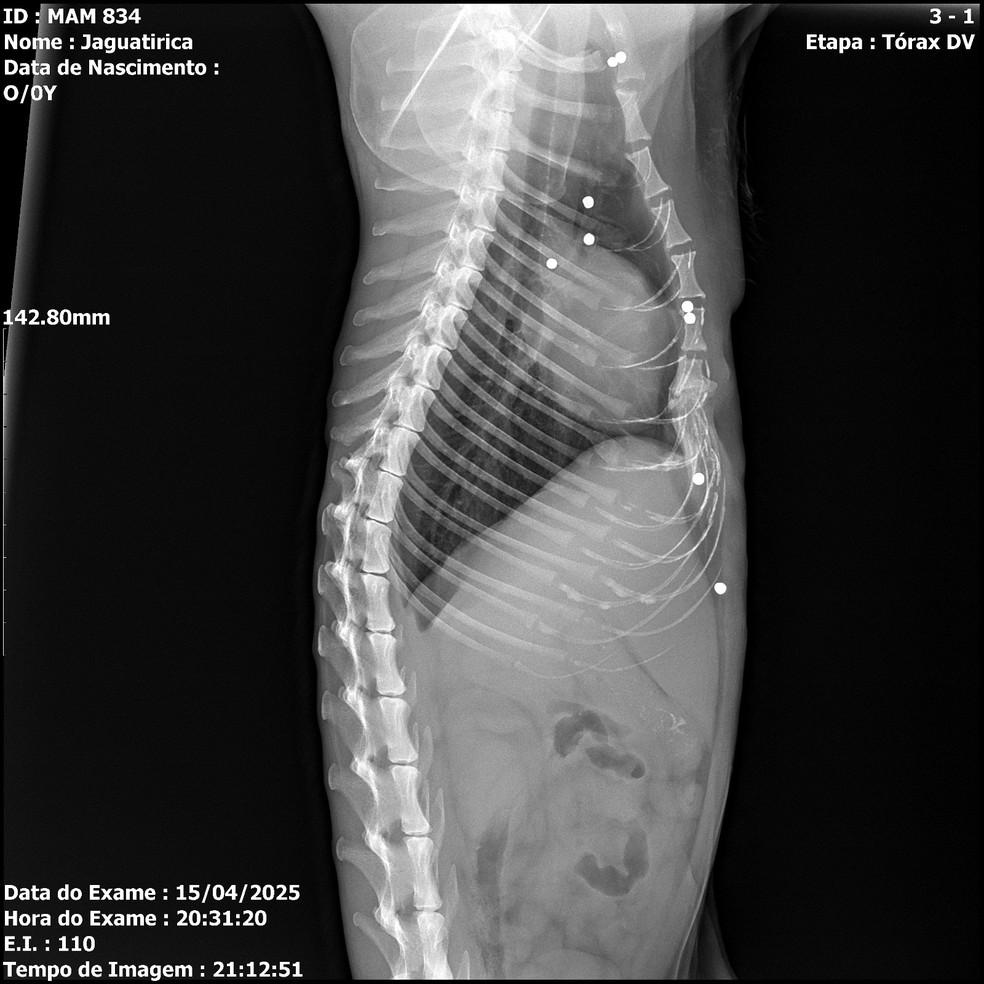

Uma jaguatirica foi resgatada no último dia 15 na região da Serra das Almas, em Trajano de Moraes, no Norte Fluminense. O animal — um macho adulto — tinha ferimentos de mais de 20 projéteis, além de fratura em na pata dianteira direita, provavelmente vítima de uma armadilha conhecida como trabuco, ocorridos dias antes do resgate, constatados por exame de raio-x. O caso foi divulgado nesta quarta-feira.

Depois de uma cirurgia em que foram retirados 23 projéteis de chumbo, um ainda está alojado perto do globo ocular: para retirá-lo, será preciso um novo procedimento cirúrgico, que depende de mais exames para apontarem a localização exata do objeto. Outras duas balas na região do tórax não serão retiradas, para não arriscar a vida do animal.

— Por que a gente sabe que foi um trabuco? Os tiros foram numa direção só. A concentração dos projéteis está na parte de barriga e do tórax — observa Paula, coordenadora de veterinária do IBW. — O animal estava magro. Para passar pela cirurgia, passou quatro dias se estabilizando, se alimentando muito bem e retiramos a maioria dos projéteis.